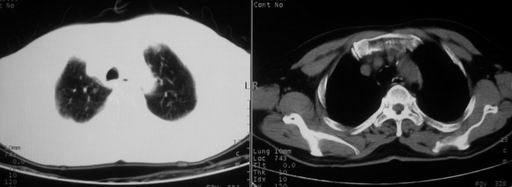

男,78岁,咳嗽、咳痰、发热入院,抗炎治疗一周后已退热,咳血似痰。

10月3日片: